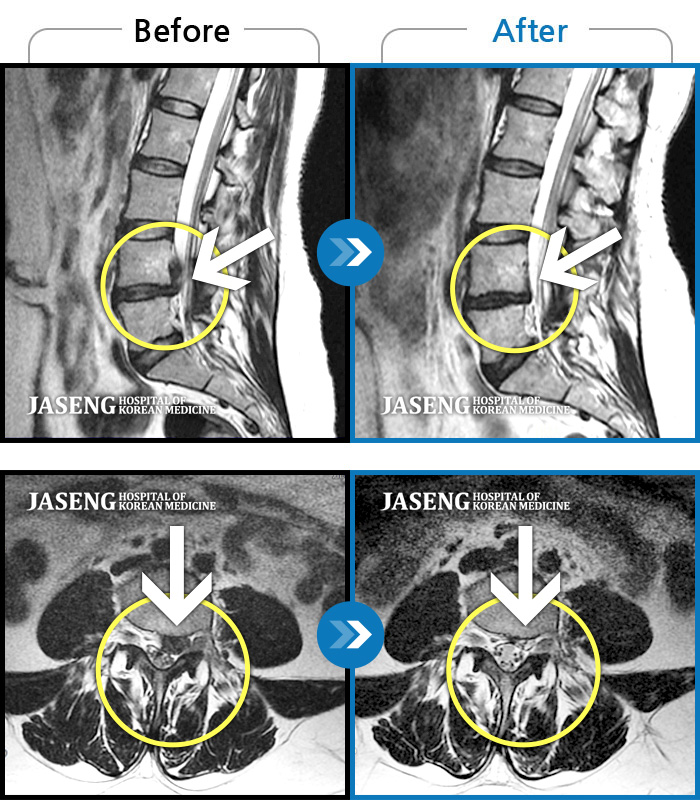

허리디스크

부천 · 최요섭 원장

허리숙이는 일을 한 후 급격하게 발생한 우측하지 방사통, 보행장애, 야간통이 있었다.

촬영시기

2023.07.29 ~ 2023.12.09

2024.01.05